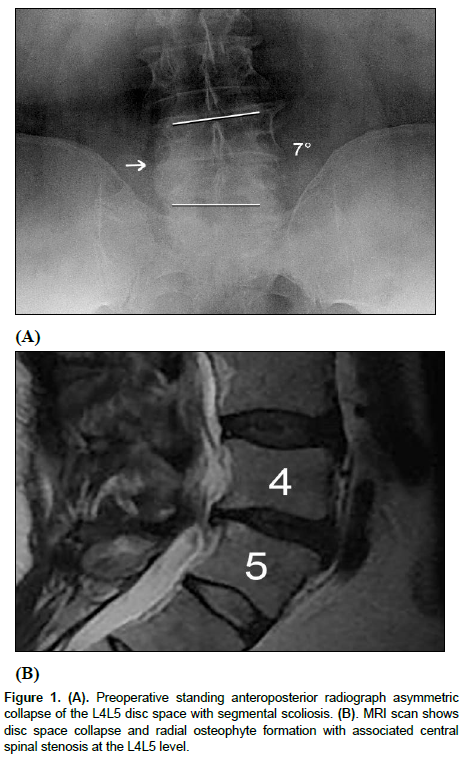

All patients showed successful radiographic fusion six months after surgery with evidence of bridging trabecular bone across the interspace forming a continuous bony connection from the superior vertebral body to the inferior vertebral body (Figures 1 and 2). In addition, there was no evidence of radiolucency involving more than 25% of the superior or inferior implant-vertebral interface. No patients had deterioration in their fusion status between the six-months and the last follow-up; all patients remained fused. There was no evidence of implant migration, subsidence, or loss of segmental lordosis at any disc level studied. There were no radiographic fusion differences in patients treated with one- or two-level fusion surgeries (Figure 3 and 4). Similarly, there were no differences in fusion outcomes regarding the PLIF or XLIF surgical approaches.

Figure 2: (A). Postoperative anteroposterior radiograph at 36 months following Posterior Lumbar Interbody Fusion at L4L5 demonstrates that the segmental scoliosis has been corrected. (B). Standing lateral radiograph shows maintenance of sagittal lordosis at L4L5 and no subsidence of the interbody implant. (C and D). Flexion and extension dynamic lateral radiographs show no motion across the fused spinal segment.